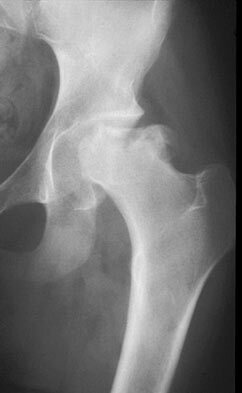

LCPD: what is the significance of hinged abduction and how is it treated?

Hinged abduction, in which lateral extrusion of the femoral head results in it impinging on the edge of the acetabulum with abduction, may be present. Treatment option include the following:

A valgus-flexion proximal femur osteotomy to place the concentric portion in contact with the acetabular roof.

Pelvic osteotomy procedures, such as a Chiari osteotomy, shelf arthroplasty, and shelf acetabuloplasty (labral support procedure), also may be beneficial but have very limited indications